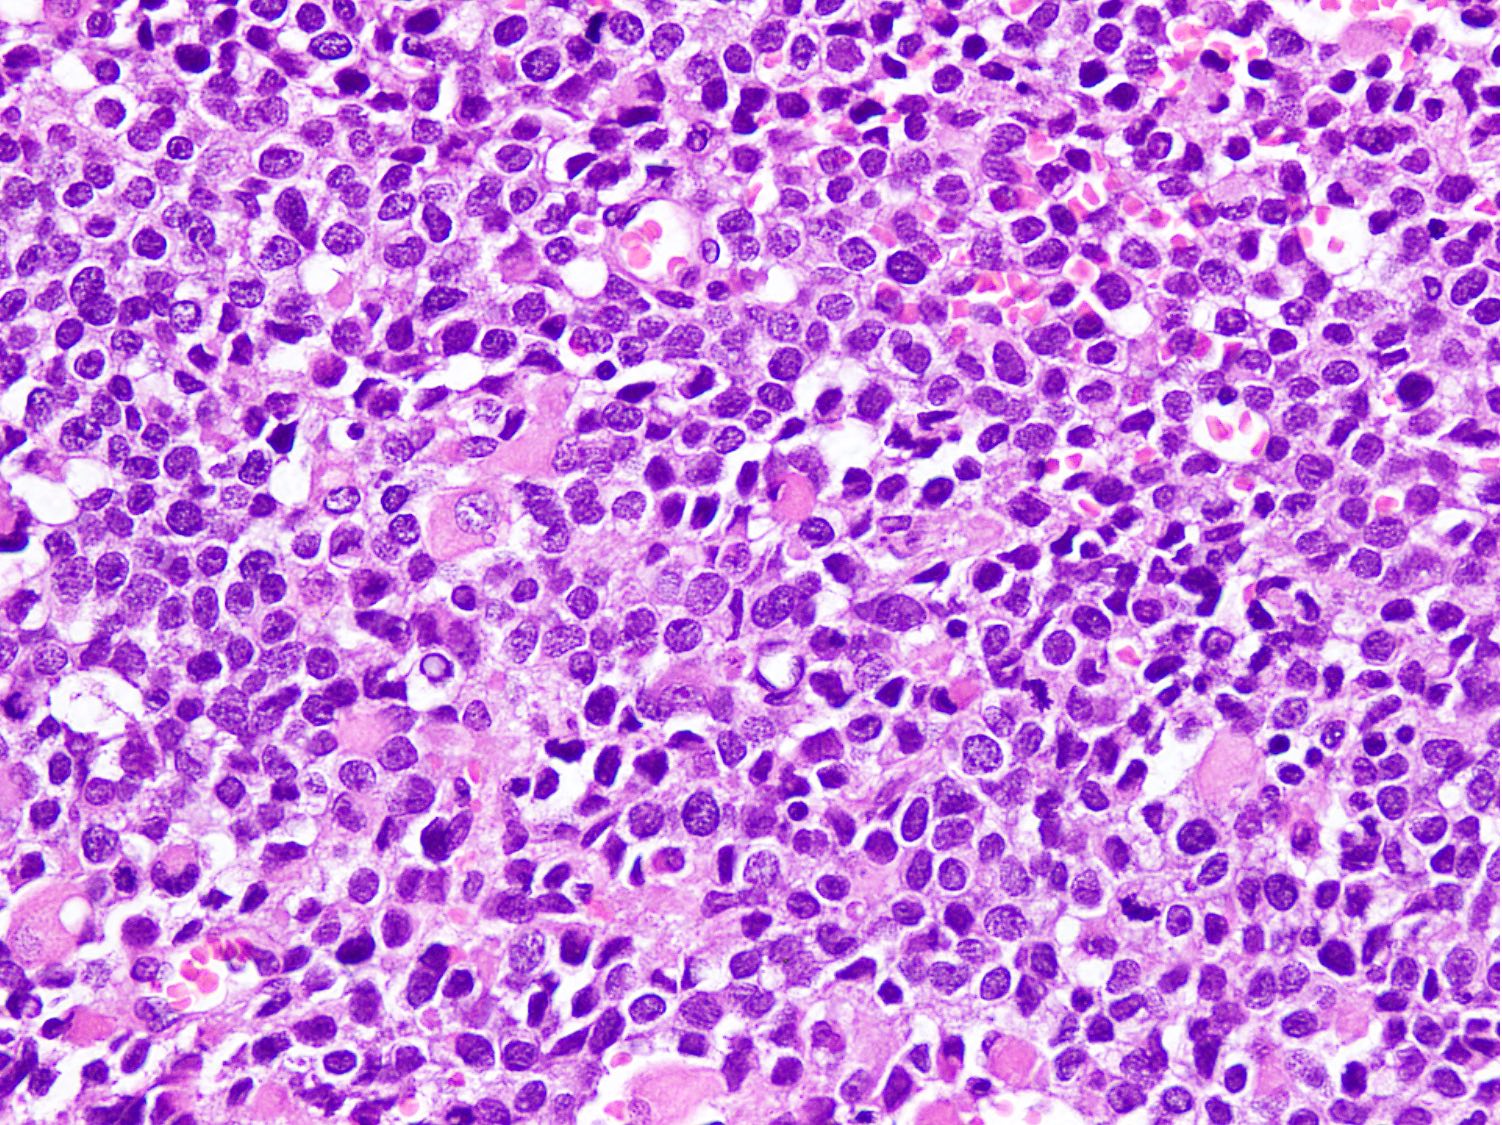

Microscopic (histologic) description

- Small to intermediate sized monomorphic cells with scant cytoplasm

- Hyperchromatic nuclei with variable conspicuous small nucleoli

- Cells in the center have poor preservation and are necrotic; may appear floating

- Multinucleated tumor giant cells with wreath-like lineup of nuclei are common (Acta Pathol Microbiol Immunol Scand A 1982;90:345)

- Round to oval rhabdomyoblasts with abundant acidophilic cytoplasm may be present

- Brisk mitosis and variable tumor necrosis

- Occasional cases may show clear cell morphology with pale, glycogenated cytoplasm

- Rare anaplasia

Microscopic (histologic) images

Contributed by Nasir Ud Din, M.B.B.S.